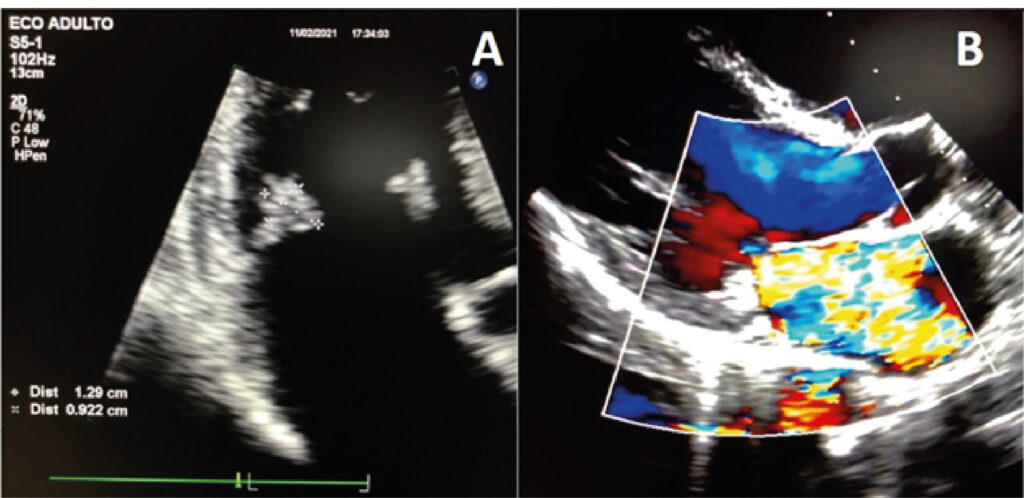

Endocardite de Libman-Sacks em Paciente Masculino com Lúpus Eritematoso Sistêmico

A endocardite de Libman-Sacks (ELS), também conhecida como endocardite marântica ou verrucosa, é uma forma de endocardite trombótica não bacteriana (ETNB) que envolve a presença de vegetações estéreis nas valvas cardíacas. Essas vegetações podem estar associadas com malignidade, lúpus eritematoso sistêmico (LES) ou síndrome do anticorpo antifosfolipídeo (SAAF) e são mais comumente encontradas nas valvas mitral e aórtica, mas outras valvas podem estar envolvidas. O diagnóstico exige alta presunção clínica na avaliação de populações específicas.